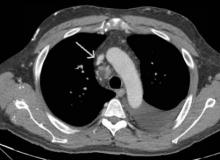

[4]Figure 2. Axial chest CT demonstrating occlusive stenosis of the central portion of the innominate vein and SVC confluence.

Given his chronic immunosuppression, he was admitted by internal medicine for initiation of intravenous (IV) antibiotics. Thoracic surgery, transplant infectious disease, and nephrology were consulted following admission. He underwent an echocardiogram, which did not demonstrate congestive heart failure. A computed tomography (CT) scan demonstrated right internal jugular occlusion, superior vena cava (SVC) stenosis, prominent thoracic venous collaterals, and cervical and mediastinal lymphadenopathy (Figures 1 and 2). His pleural fluid cytology and cultures were negative, but testing indicated the presence of chylomicrons and his triglyceride level was 1154 mg/dL, which was consistent with a chylothorax.